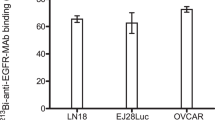

Impact of BTK inhibition on cell metabolism

Next, we performed LC‒MS-based metabolomics using two cell lines with moderate (REC-1) and high (MCL-RL) IBR sensitivity. We performed untargeted steady-state polar metabolite profiling on these two cell lines and treated them with DMSO alone or with IBR-DMSO for 24 h. LC‒MS identified 166 and 185 polar metabolites in REC-1 and MCL-RL cells, respectively. Using a p-value < 0.05 and a fold change (FC) cutoff of ± 1.5, we selected 77 metabolites from REC-1 and 51 from MCL-RL for further pathway analysis. The IBR impaired a large spectrum of metabolic pathways in the two MCL cell populations, including pyrimidine and purine synthesis; the tricarboxylic acid (TCA) cycle; the pentose shunt; glycolysis; and the synthesis of the amino acids alanine, aspartate, and glutamate (Fig. 2a, and Figs. S6, and S7). Among the affected metabolic pathways, glycolysis/pyruvate metabolism/Warburg effect and alanine metabolism attracted our attention because we were able to detect the related metabolites lactate and alanine in intact cells using 1H MRS imaging [6]. Fig. S6 also shows the accumulation of choline, another metabolite detectable by in vivo 1H MRS as part of the total choline complex, which is typically dominated by phosphocholine [16].

BTK inhibition-mediated suppression of metabolic pathways and extracellular lactate flux. a Impact of BTK inhibition on cell metabolism in sensitive MCL cells. The highlighted metabolic pathways affected in REC-1 and MCL-RL cells by their treatment with IBR have been identified by LC–MS and metabolome-targeting bioinformatics. b Impact of BTK inhibition in MCL cells on extracellular lactate. The depicted four MCL cell lines that differ in their sensitivity to BTK inhibition (Fig. 1a) were cultured with 500 nM of BTK inhibitor IBR and examined at the indicated time points for lactate concentration by using YSI 2300 biochemical analyzer. All experiments were performed in triplicates and the data are presented as mean ± SEM. with the p-values of statistical significance indicated

Notably, the impairment of glycolysis and amino acid metabolism directly correlated with the BTK inhibition-mediated suppression of the mRNA expression of the key enzymes involved in these processes and the related oxidative phosphorylation, as observed in the REC-1 and MCL-RL cells (Supplemental Tables S1 and S2, respectively). The above findings indicate that BTK induces the expression of these metabolic enzymes and that the BTK inhibition-mediated decrease in the synthesis of lactate (a product of mainly glycolysis) and alanine (an indicator of amino acid metabolism) is due, at least in part, to the suppression of the expression of genes encoding enzymes involved in metabolism.

Effect of BTK inhibition on lactate metabolism

1H MRS imaging-based detection of BTK inhibition-mediated decreases in lactate, alanine, and total choline concentrations

Next, we analyzed the effects of IBR on lactate and alanine levels using 1H MRS-based imaging. We also examined the concentration of total choline, which is predominantly affected by phospho-choline [6], since the accumulation of choline as a substrate was observed via metabolomic analysis (Fig. S6), as well as our ability to detect total choline via 1H MRS (Fig. 3b).

IBR affected the lactate and alanine concentrations in MCL cells (Fig. 3b) proportionately to the degree of cell growth inhibition (Fig. 1a), with MCL-RL and REC-1 showing profound inhibition of lactate and alanine concentrations, JeKo-1 displaying a borderline effect for lactate and no visible effect for alanine, and MCL-SL showing no inhibition. Regarding total choline, MCL-RL cells displayed a profound IBR-mediated reduction, REC-1 and JeKo-1 showed a decreasing trend, while MCL-SL exhibited no change. In contrast to the changes in lactate, alanine, and total choline concentrations, we did not observe significant changes in taurine concentrations in any of these MCL cell populations (data not shown), confirming that BTK inhibition exerts a broad but not universal impact on tumor metabolism (Fig. 2a, and Figs. S6, and S7).